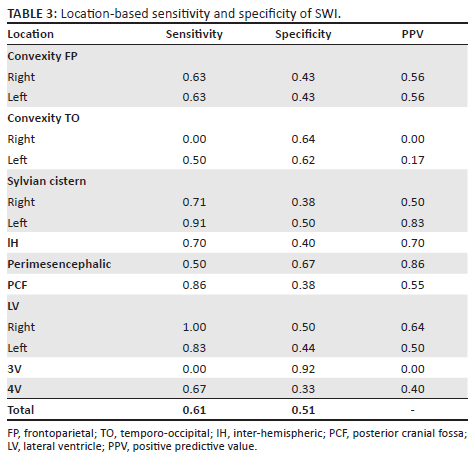

CT versus MRI

In those patients with both SWI and available initial NECT images (15 patients), 390 zones were analysed (195 CT and 195 SWI zones). Of the total 195 zones on CT, 86 positive haemorrhage zones were identified. Of the total 195 zones on SWI, 108 positive haemorrhage zones were detected (Table 2). Overall, SWI (108 regions) detected more regions than CT (86 regions) with a global sensitivity of 61% and specificity 51% per location (Table 3).

Convexity

Overall, SWI detected more regions of haemorrhage than the initial CT (as depicted in Figure 2) with a location-based sensitivity of 56% and specificity of 50%. A previous study by Mulé with T2* showed a similar sensitivity of 64% with an improved specificity of 82%.16 The marked difference in specificity was unanticipated and thought to be because of CSF flow dynamics causing haemorrhage to be washed to more regions remote from the site of rupture and hence detected on imaging in the chronic phase.12,13,16

Basal Cisterns

This study showed a sensitivity of 50% in the perimesencephalic cistern, exceeding that of previous studies with T2* of 8%.16 The poor sensitivity in this region was because of regional artefact from the base of skull and high CSF flow displacing any haemorrhage as depicted in Figure 3.12,13,16,17,18

Ventricular System

Previous T2* studies in chronic ASAH showed poor sensitivities in the detection of haemorrhage in the ventricular system. Mulé et al. demonstrated a sensitivity of 10%.16 This was thought to be related to high CSF flow velocities in these locations, preventing adequate time for haemosiderosis.12,13,16 The current study contradicted this with increased sensitivity of 62.5% for haemosiderin, even exceeding regions seen on the initial NECT as depicted in Figure 4. These areas of haemosiderin identified on SWI were located in the dependent regions of the ventricular system (occipital horns of the lateral ventricles and dependent lateral recesses of the 4th ventricle).

Two postulated reasons were thought to account for this. Firstly, the inherent increased sensitivity and high-resolution imaging of SWI compared with T2* resulted in a greater sensitivity. Secondly, over time there is reflux of haemorrhage from the cisterns into the ventricular system in patients with subarachnoid haemorrhage as shown in previous studies.8,19 This process is thought to occur to equalise CSF pressures and may show haemosiderin in the ventricular system in patients who initially did not have intraventricular haemorrhage.

Infratentorial

Studies by Falter et al. and Mulé et al. showed T2* detection rates of haemosiderin in chronic ASAH in the infratentorial cisterns approaching 70% - 90%.12,16 Despite this, Lummel et al. and Mulé et al. demonstrated poor sensitivity of haemosiderin on T2* in the infratentorial compartment 10% - 21.9%.14 Susceptibility artefact in these sequences is related to the strength of the MRI magnetic field and previous surgical washout. However, Lummel et al. utilised a 3T machine similar to the other studies and the majority of patients underwent endovascular repair. A reason to account for the discrepancy in these studies is unknown.

In comparison, the current study showed high haemosiderin detection, with a sensitivity of 86% in the infratentorial compartment, exceeding that of the initially detected haemorrhage on NECT (SWI 11; CT 7) as depicted in Figure 5. This is most likely because of CSF flow as described by Koeppen et al., who showed in CSF flow studies that the brainstem and cerebellar convexities initially receive preferential CSF flow and serve as a site of haemosiderin deposition, albeit remote to the site of rupture. This has been described in patients with recurrent subarachnoid haemorrhage causing superficial haemosiderosis.